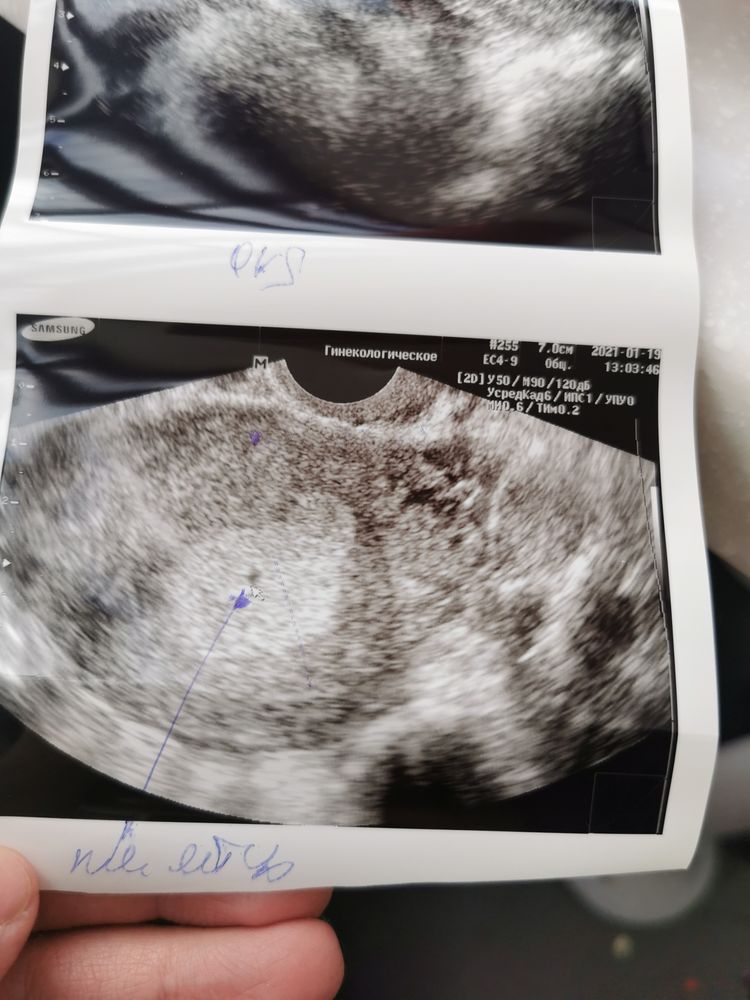

УЗИ 😊🤰🏻🙌🏻

Решила я сходить на УЗИ)

Имплантация произошла 6 января, у меня тогда ещё были дикие боли в спине и животе